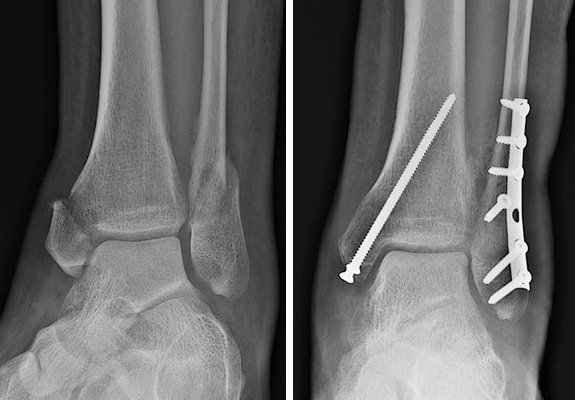

2) 수술치료(발목골절 수술이 필요할 때)

다음과 같은 경우에는 **수술적 치료(내고정술 등)**를 고려하게 됩니다.

- 골절 조각이 어긋난 경우(전위)

- 발목 관절의 맞물림(정렬)이 무너진 경우

- 불안정 골절(인대 손상 동반 등)로 고정 없이는 유지가 어려운 경우

- 관절면을 포함한 골절로 **정확한 정복(맞춤)**이 필요한 경우

발목골절 수술은 단순히 “붙이는 수술”이 아니라, 발목 관절의 정렬을 최대한 정확히 복원하는 것이 핵심입니다.